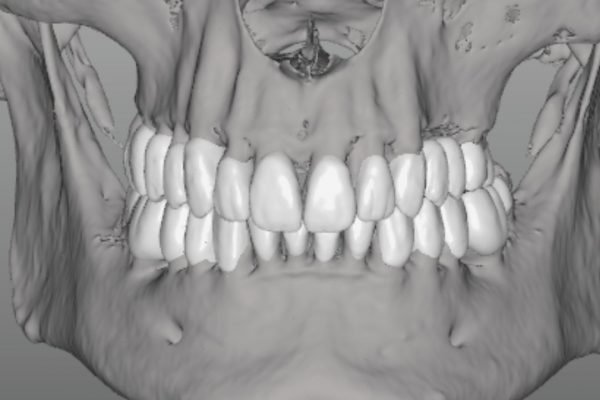

En la actualidad, la tecnología en odontología ha permitido realizar estos tratamientos de manera más eficiente y cómoda para el paciente. La técnica del Clon digital o Paciente Virtual, por ejemplo, permite obtener un modelo digital dinámico del paciente, lo que permite diseñar todo el tratamiento digitalmente y utilizar bibliotecas de dientes naturales para obtener un resultado estético y funcionalmente óptimo. Gracias a esta técnica, se pueden realizar tratamientos en menos citas y con mayor comodidad para el paciente.